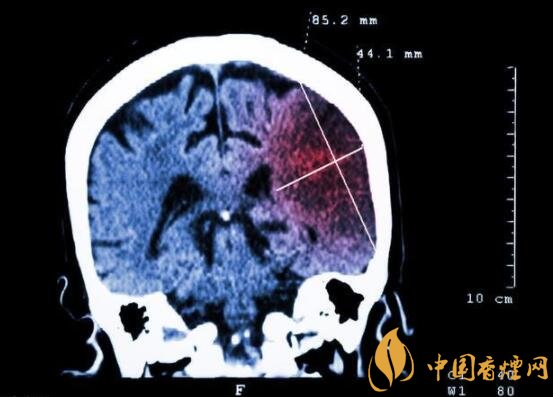

一般而言,急性腦梗塞與長期吸煙有非常密切的聯(lián)系。有長期煙齡遇到肢體活動不順,做頭顱核磁共振檢查往往查出一側(cè)大腦中動脈閉塞的可能性很高。由此可見,吸煙確實與中風存在一定聯(lián)系。